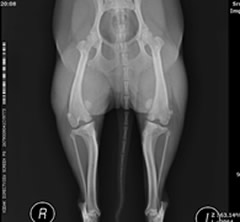

膝蓋骨内方脱臼

両側性の膝蓋骨内方脱臼により持続した跛行がありました。しかし、飼い主様は足の異常に気づいておらず、ワクチン接種時に判明しそのまま手術となりました。小型犬に多いトラブルですので、獣医師に触診してもらうだけでもおおよその異常は見つけられるハズです。

術後:膝蓋骨内方脱臼

この他、内側広筋解離術、脛骨粗面外方移植術、外側関節包・膝蓋支帯の縫縮術を施し手術終了です。